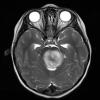

Diffuse midline glioma, H3 K27-altered (11)